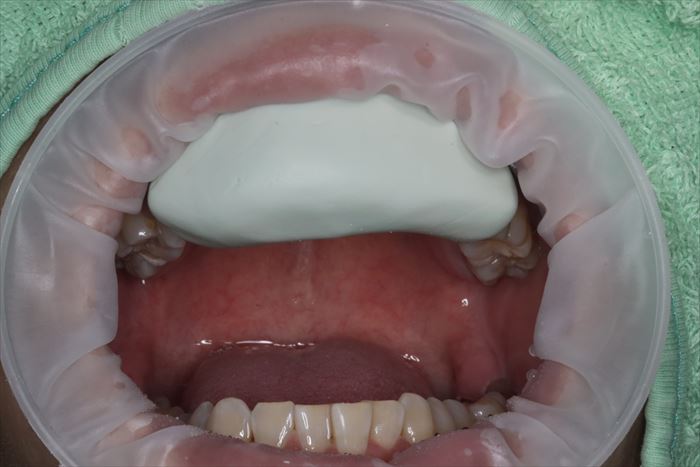

口蓋側面観ミラー像です。仮歯が両サイドの歯に固定されており、仮歯と歯根の間は浮いている状態です。